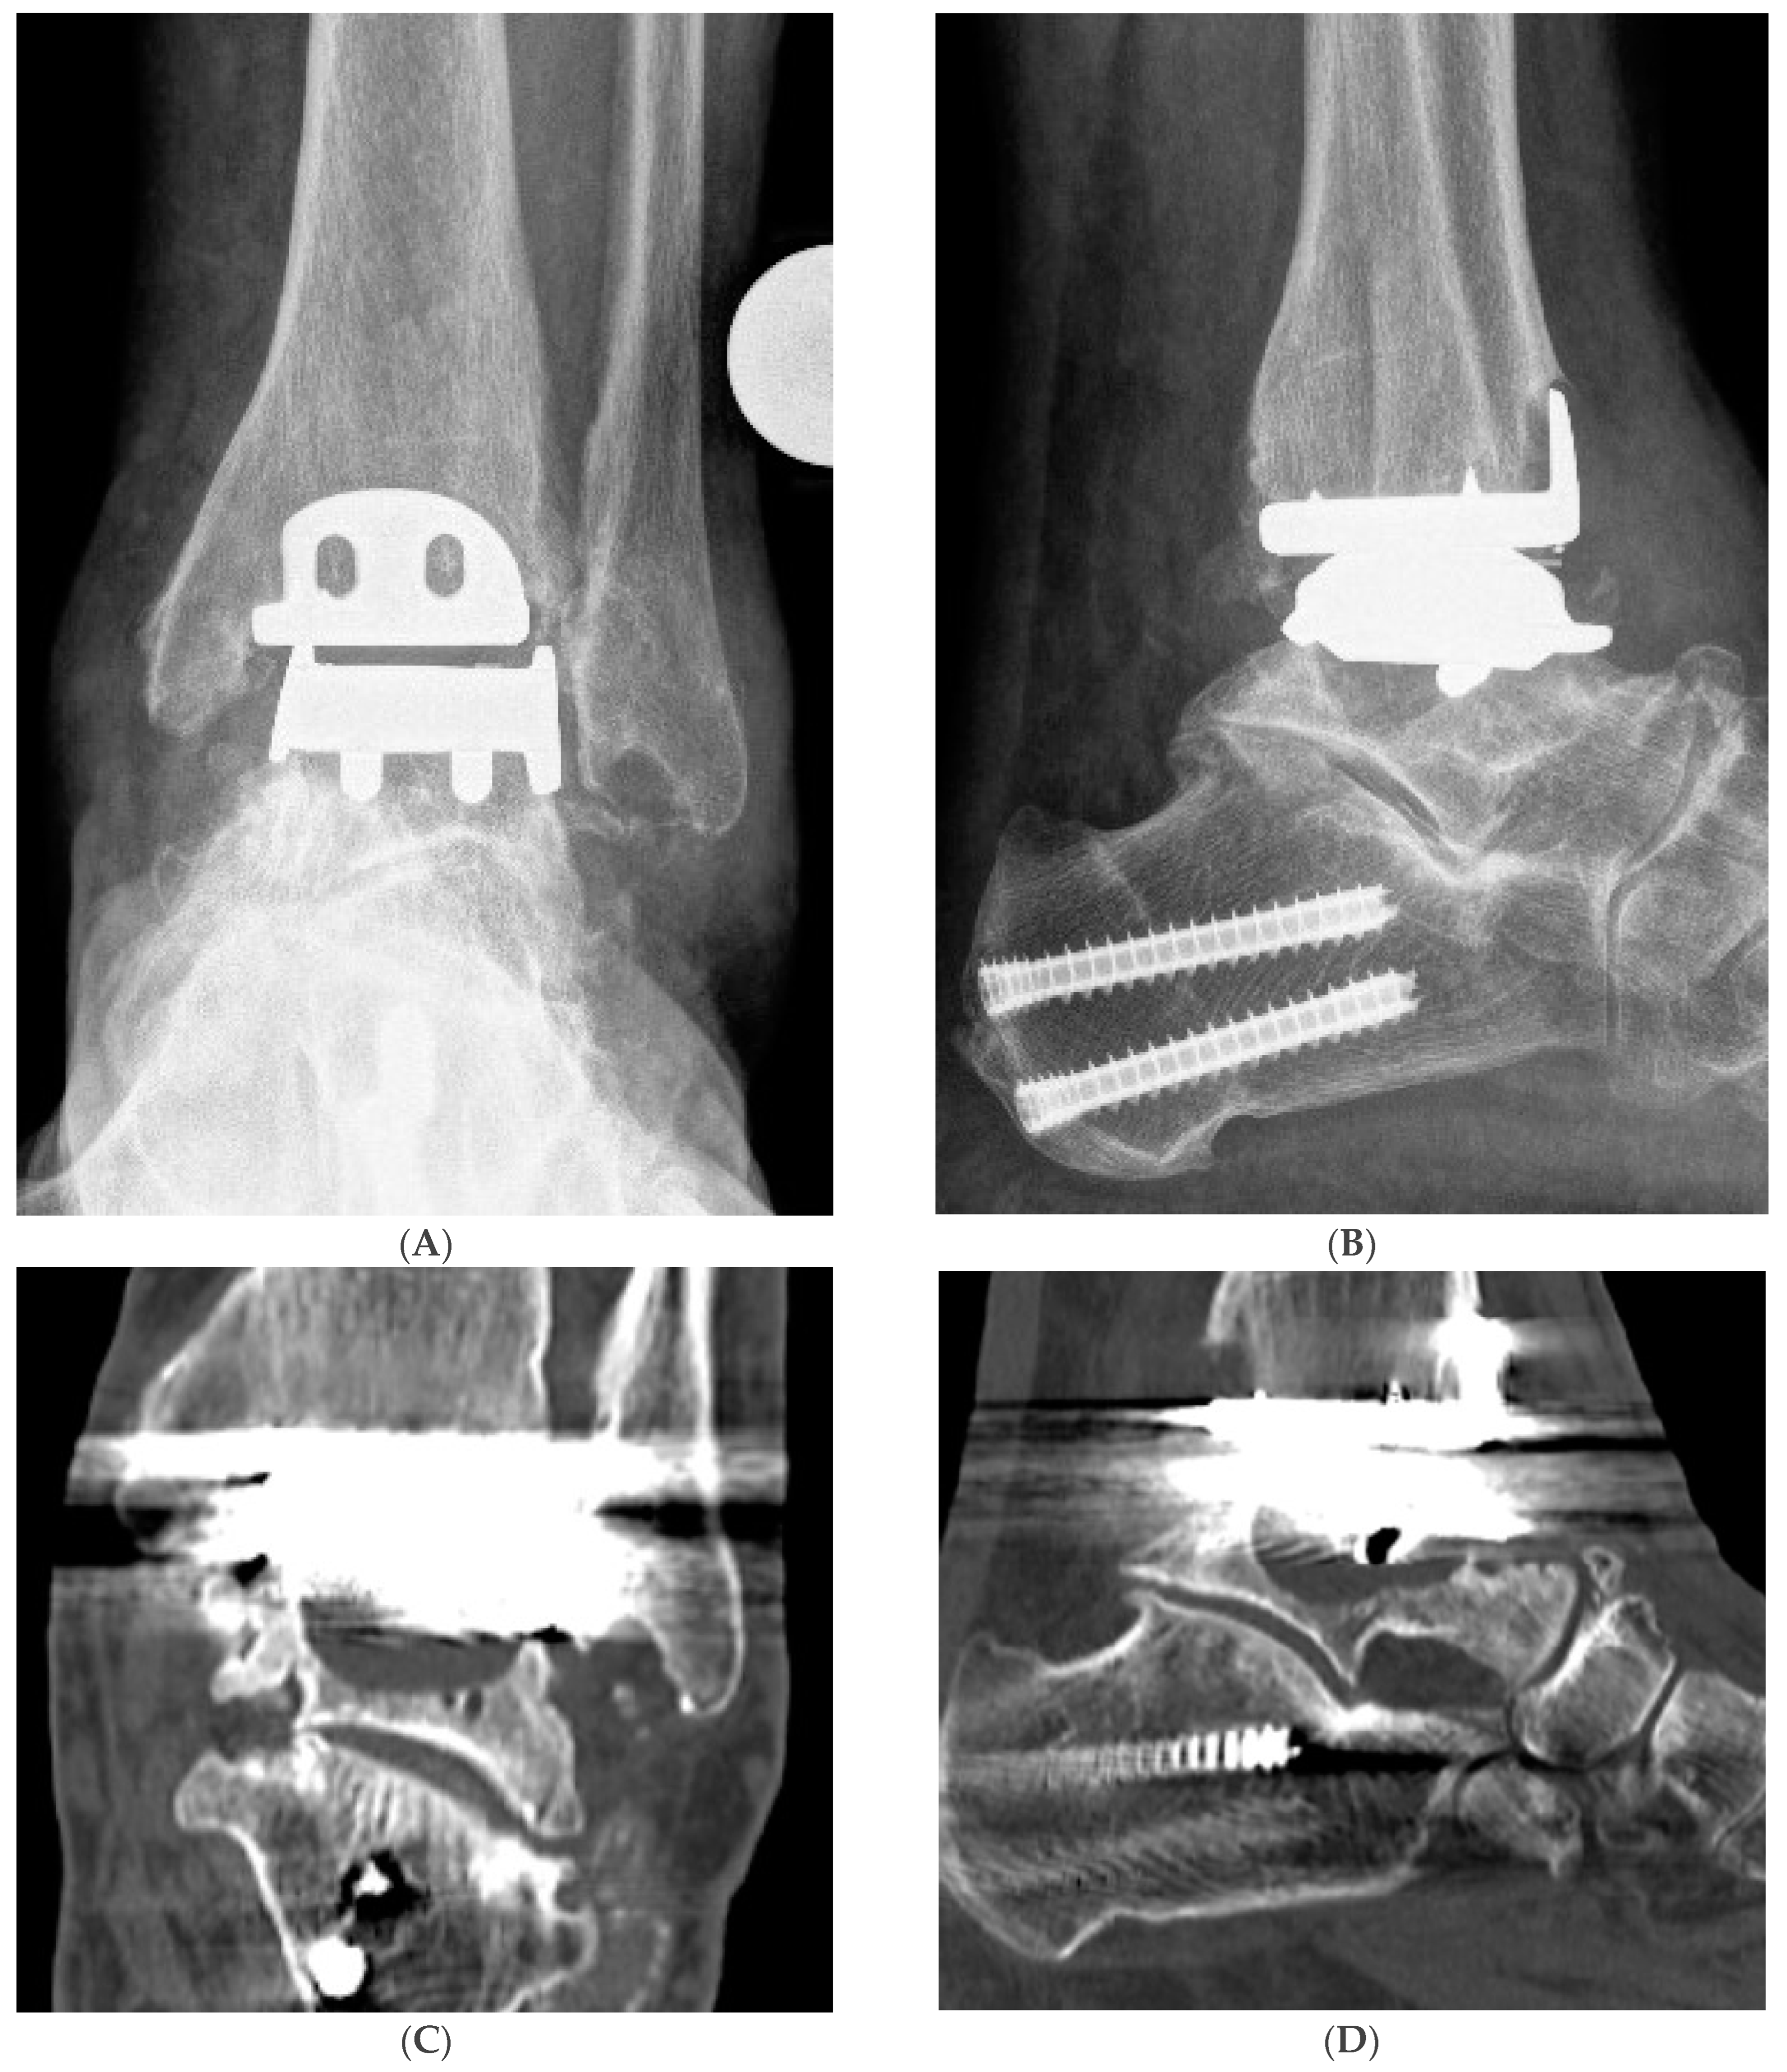

2. Materials and Methods

Surgical Procedure